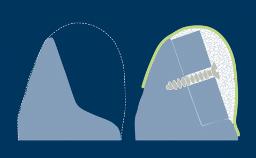

Introduction to Implant Dentistry

Implant Designs and Characteristics

Learning Module